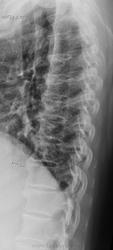

Пол пациента: Женский пол Тип патологии: Метаболическое заболевание Область исследования: Скелетно-мышечная система Методы исследования: Rg Синдесмофиты по боковой поверхности позвонков Th IV - Th11. Болезнь Форестье? https://radiomed.ru/sites/default/files/styles/case_slider_image/public/user/19785/f_t_spine_20140325_110901.jpg?itok=rvYoDwaG ID:36388 Tue, 25/03/2014 - 19:22 #1 Dima Offline Last seen: 7 years 4 months ago Joined: 05.08.2012 - 17:39 Posts: 2467 Форестье нет. Возможно болезнь Бехтерева. Терпимость - это когда прощают чужие ошибки; такт - когда не замечают их. (Артур Шницлер) Tue, 25/03/2014 - 19:49 #2 maker4ik Offline Last seen: 8 years 9 months ago Joined: 19.10.2011 - 17:49 Posts: 2682 Форестье или Бехтерева. Доснимите ИСС. Tue, 25/03/2014 - 20:16 #3 И.Бондаренко Offline Last seen: 5 days 4 hours ago Joined: 13.09.2011 - 22:55 Posts: 9208 Если в анализах СОЭ повышено, и есть сакроилеит и заращение межпозвонковых суставов (проекция в 3/4) - то скорее Бехтерева. А так Форестье. Tue, 25/03/2014 - 21:08 #4 Андрей Юрьевич Offline Last seen: 3 weeks 3 days ago Joined: 16.11.2008 - 22:16 Posts: 18101 перчик wrote: ... Болезнь Форестье?Или? Андрей Юрьевич Tue, 25/03/2014 - 21:49 #5 Dima Offline Last seen: 7 years 4 months ago Joined: 05.08.2012 - 17:39 Posts: 2467 И.Бондаренко wrote: Если в анализах СОЭ повышено, и есть сакроилеит и заращение межпозвонковых суставов (проекция в 3/4) - то скорее Бехтерева. А так Форестье. Как так? Почему форестье, связка на уровне тел не окостенелая... Терпимость - это когда прощают чужие ошибки; такт - когда не замечают их. (Артур Шницлер) Sat, 14/10/2017 - 08:44 #6 Катенёв Валенти... Offline Last seen: 7 years 2 months ago Joined: 22.03.2008 - 22:15 Posts: 54876 Dima wrote: Форестье нет. + Wed, 11/04/2018 - 16:59 #7 NataSey Offline Last seen: 7 years 10 months ago Joined: 11.04.2018 - 16:54 Posts: 2 Здравствуйте. Я перевожу мед.заключение. Помогите, пожалуйста, с расшифровкой ИСС. Речь идет о сцинтинрафии костей скелета. Огромное спасибо!!! Wed, 11/04/2018 - 17:28 #8 NIL Offline Last seen: 1 month 3 weeks ago Joined: 25.11.2013 - 20:50 Posts: 18208 NataSey wrote: Помогите, пожалуйста, с расшифровкой ИСС. ИСС= Илеосакральные сочлениения(если правильно понят вопрос) "Слушай всех, прислушивайся к немногим, решай сам".© Thu, 12/04/2018 - 08:22 #9 NataSey Offline Last seen: 7 years 10 months ago Joined: 11.04.2018 - 16:54 Posts: 2 Да.Большое спасибо Вам!!!!

Форестье нет. Возможно болезнь Бехтерева.

Форестье или Бехтерева. Доснимите ИСС.

Если в анализах СОЭ повышено, и есть сакроилеит и заращение межпозвонковых суставов (проекция в 3/4) - то скорее Бехтерева. А так Форестье.